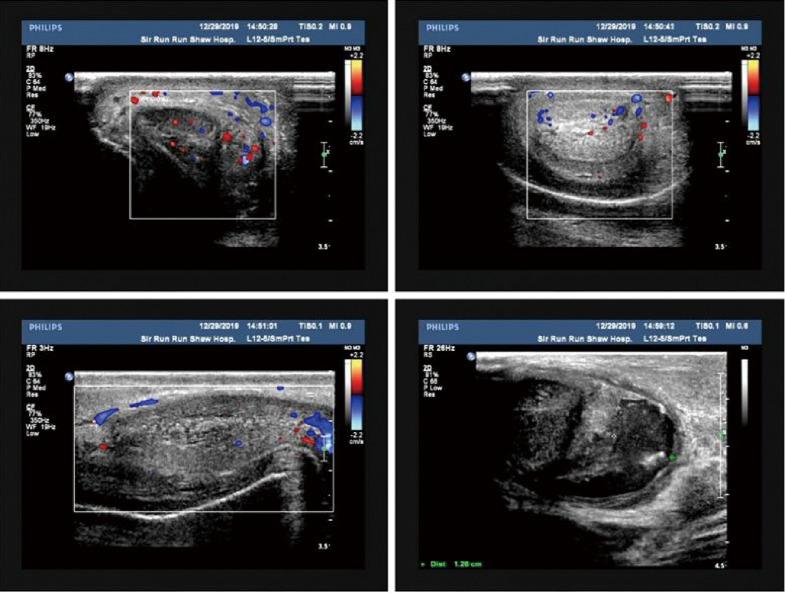

Penile fracture is described as a traumatic rupture of the tunica albuginea caused by blunt injury to the erect penis. It usually occurs as a single rupture of the tunica albuginea in one of two corpora cavernosa; a rupture with urethral injury is an extremely rare condition. Although its diagnosis is usually clinical, ultrasound plays an important role in confirming diagnosis and identifying the site of the injury. Here, we presented a case of penile fracture with complete urethral injury. A 43-year-old male was admitted to the hospital because of trauma to the genital and dysuria following sexual intercourse. After admission, the patient was diagnosed with double penile fracture and complete urethral injury after the physical and B-ultrasound examinations. Emergency surgery to remove the hematoma and repair the urethra was performed. The patient recovered smoothly and was discharged on the third day after operation. After two months' follow-up, the patient urinated smoothly and achieved an adequate erection without other complications. In this case, consistent with previous studies, emergency surgery for penile fracture is necessary and can preserve the urethral function and sexual function. In addition, there are two lesions in tunica albuginea in this case, so careful search for the penile shaft during the surgery is important to avoid the missed injuries. This report provides evidence of an uncommon and underreported clinical case.

阴茎骨折被描述为由勃起阴茎受到钝性损伤导致的白膜创伤性破裂。它通常表现为两个海绵体之一的白膜单次破裂;伴有尿道损伤的破裂极为罕见。虽然其诊断通常依靠临床症状,但超声在确诊和确定损伤部位方面发挥着重要作用。在此,我们报告一例伴有完全性尿道损伤的阴茎骨折病例。一名43岁男性因性交后生殖器外伤和排尿困难入院。入院后,经体格检查和B超检查,患者被诊断为双侧阴茎骨折和完全性尿道损伤。遂行急诊手术清除血肿并修复尿道。患者恢复顺利,术后第三天出院。经过两个月的随访,患者排尿顺畅,勃起功能正常,未出现其他并发症。在本病例中,与既往研究一致,阴茎骨折的急诊手术是必要的,且可保留尿道功能和性功能。此外,本病例白膜有两处损伤,因此手术中仔细探查阴茎体对于避免漏诊损伤很重要。本报告提供了一个罕见且报道不足的临床病例证据。